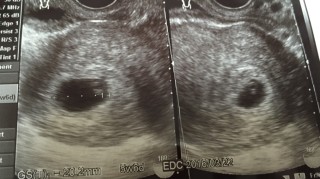

2年半の不妊治療、9回の体外授精でやっと妊娠しました。前回心拍確認後流産しているので、心配ですが、今回は出血も腹痛もなく、胎のうも前回より大きいです。先生にも、大丈夫そうですねと言われました。 胎芽の大きさは計って貰えませんでしたが、元気に動く心拍が確認できました。胎のうの大きさ2.2センチです。元気に大きく育ってね。あなたに会えるのを楽しみにしてます。